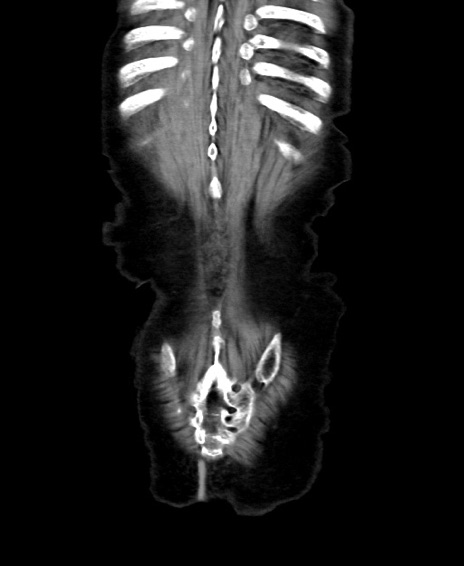

矢状断像